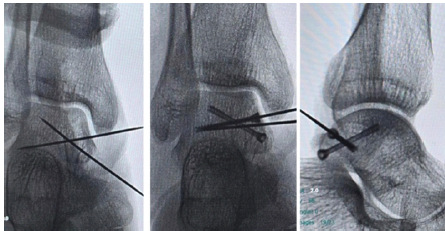

The patient underwent surgery 1 day post-injury under spinal anesthesia in the prone position. A straight posteromedial incision was made just medial to the Achilles tendon (Fig. 3).

Figure 3: Intraoperative image showing posteromedial approach and white arrow showing fractured posteromedial talar process.The approach developed the interval between the flexor hallucis longus tendon laterally and the posterior tibial neurovascular bundle medially. The fracture fragment was exposed, anatomically reduced and temporarily fixed with a 1.5 mm K-wire. Under fluoroscopic guidance, two 3.0 mm Herbert screws were placed for definitive fixation (Fig. 4).

Figure 4: C-arm images showing placement of guide wires and Herbert screws.